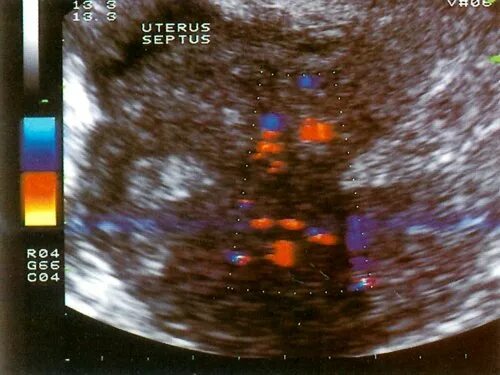

Локусы при цдк что это